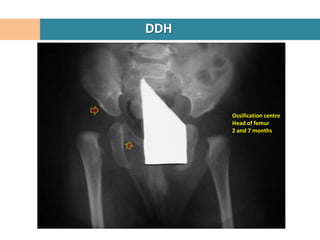

DDH

Ossification centre

Head of femur

2 and 7 months